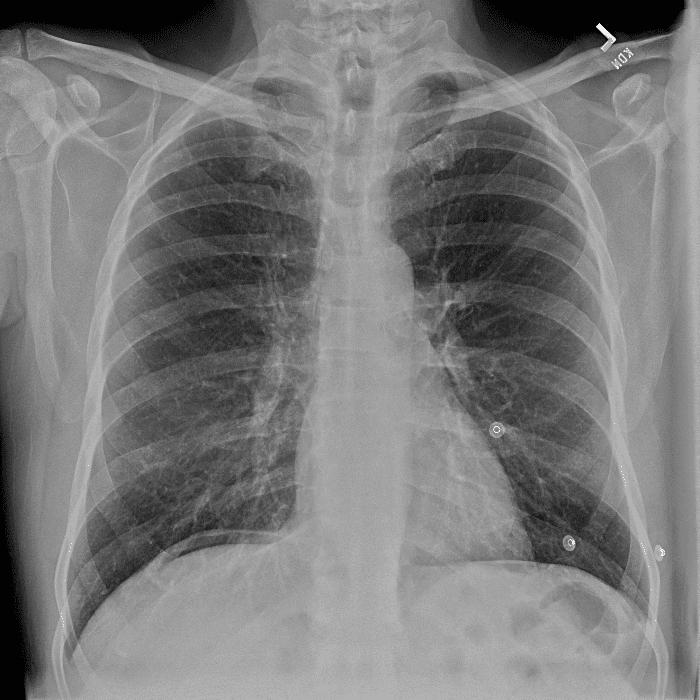

Practice Cases